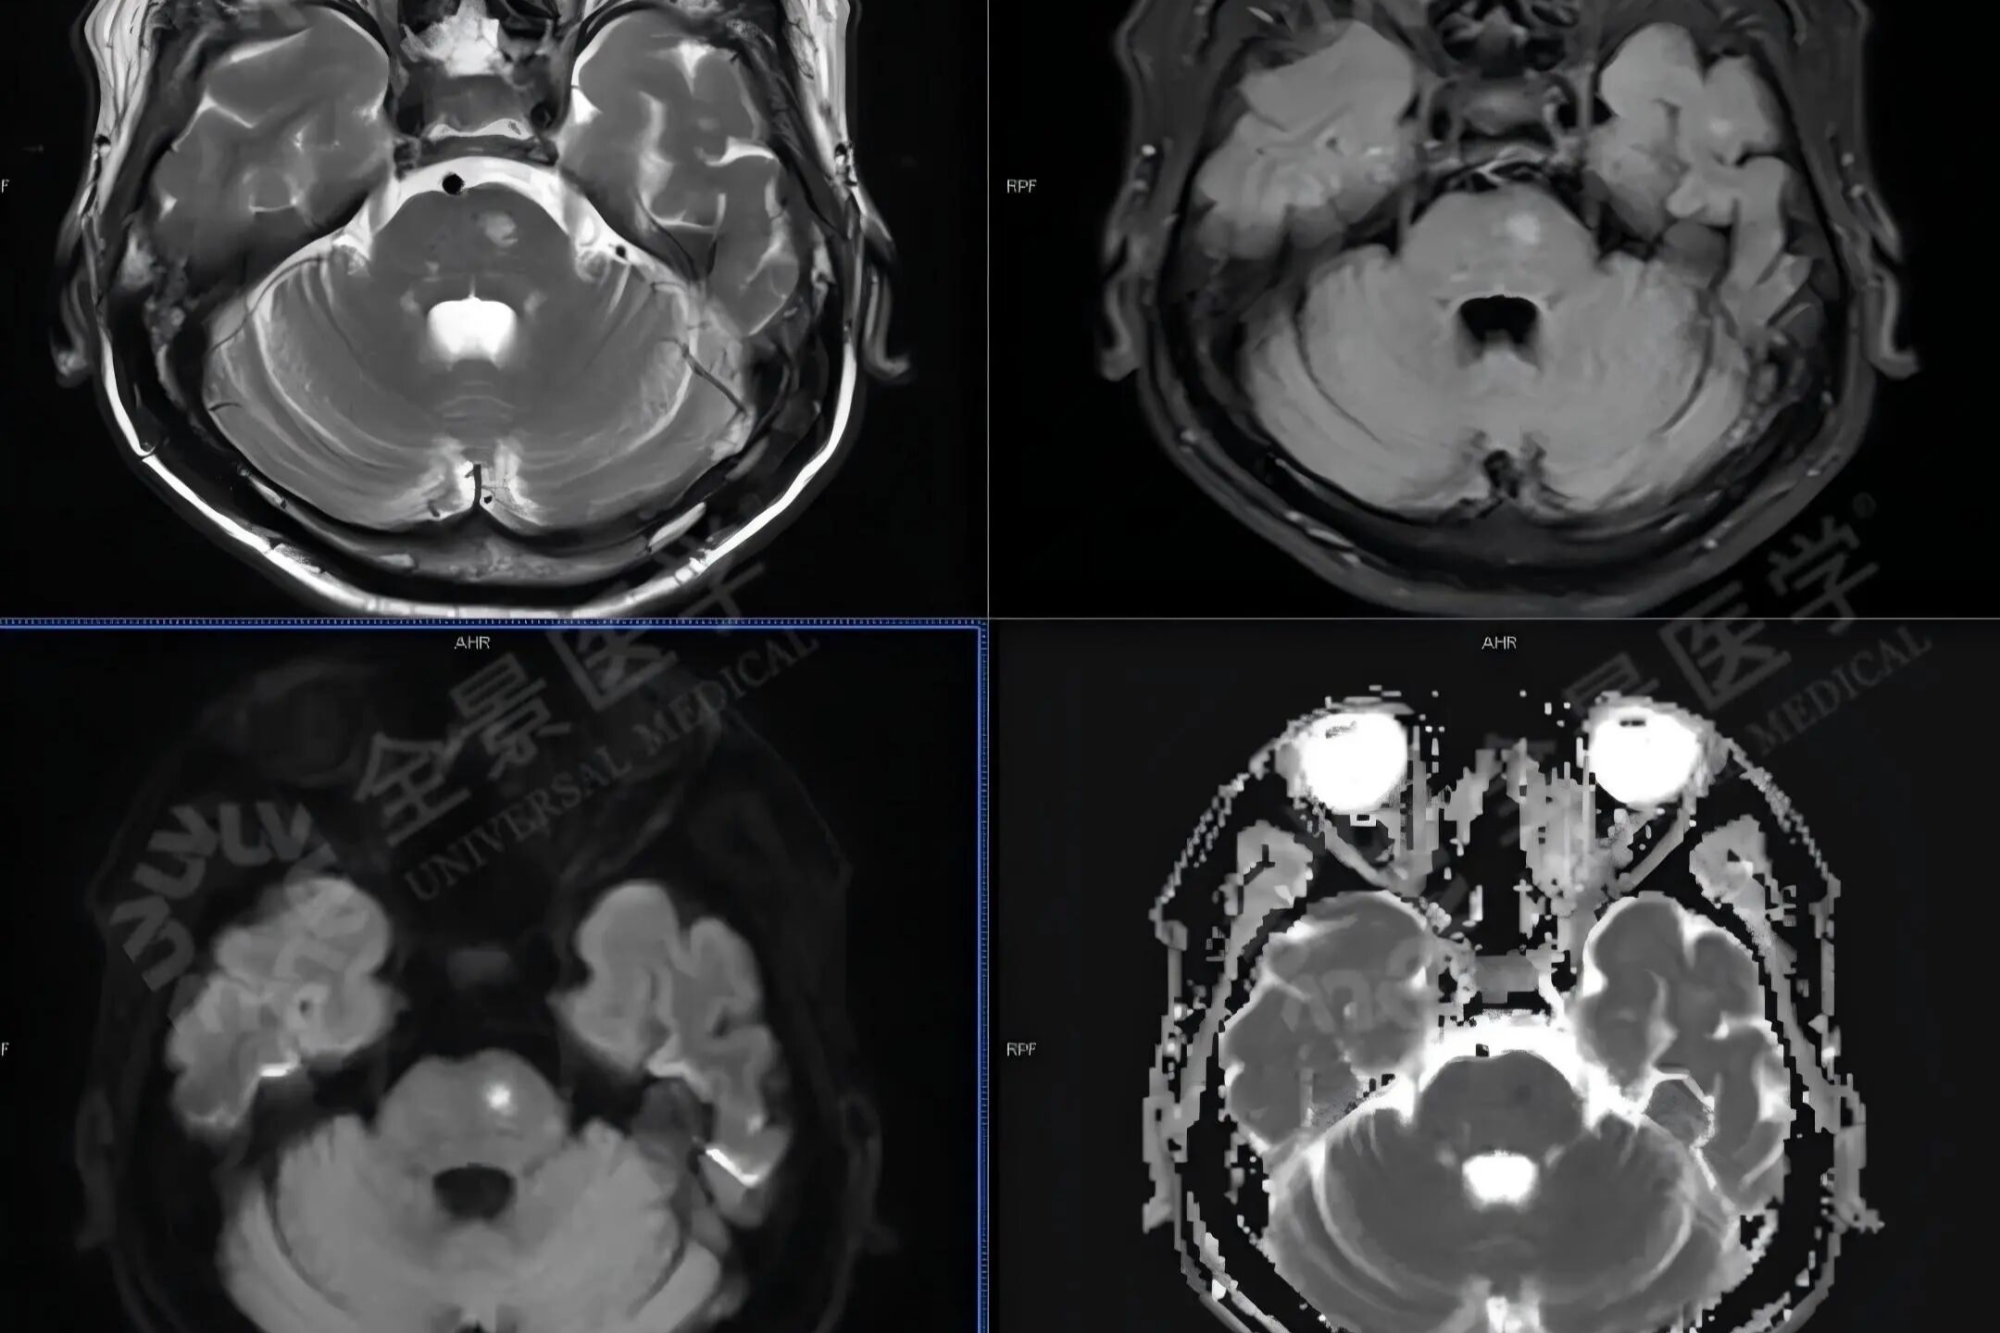

淋巴瘤治疗显成效!PET/CT 见证病灶「大撤退」